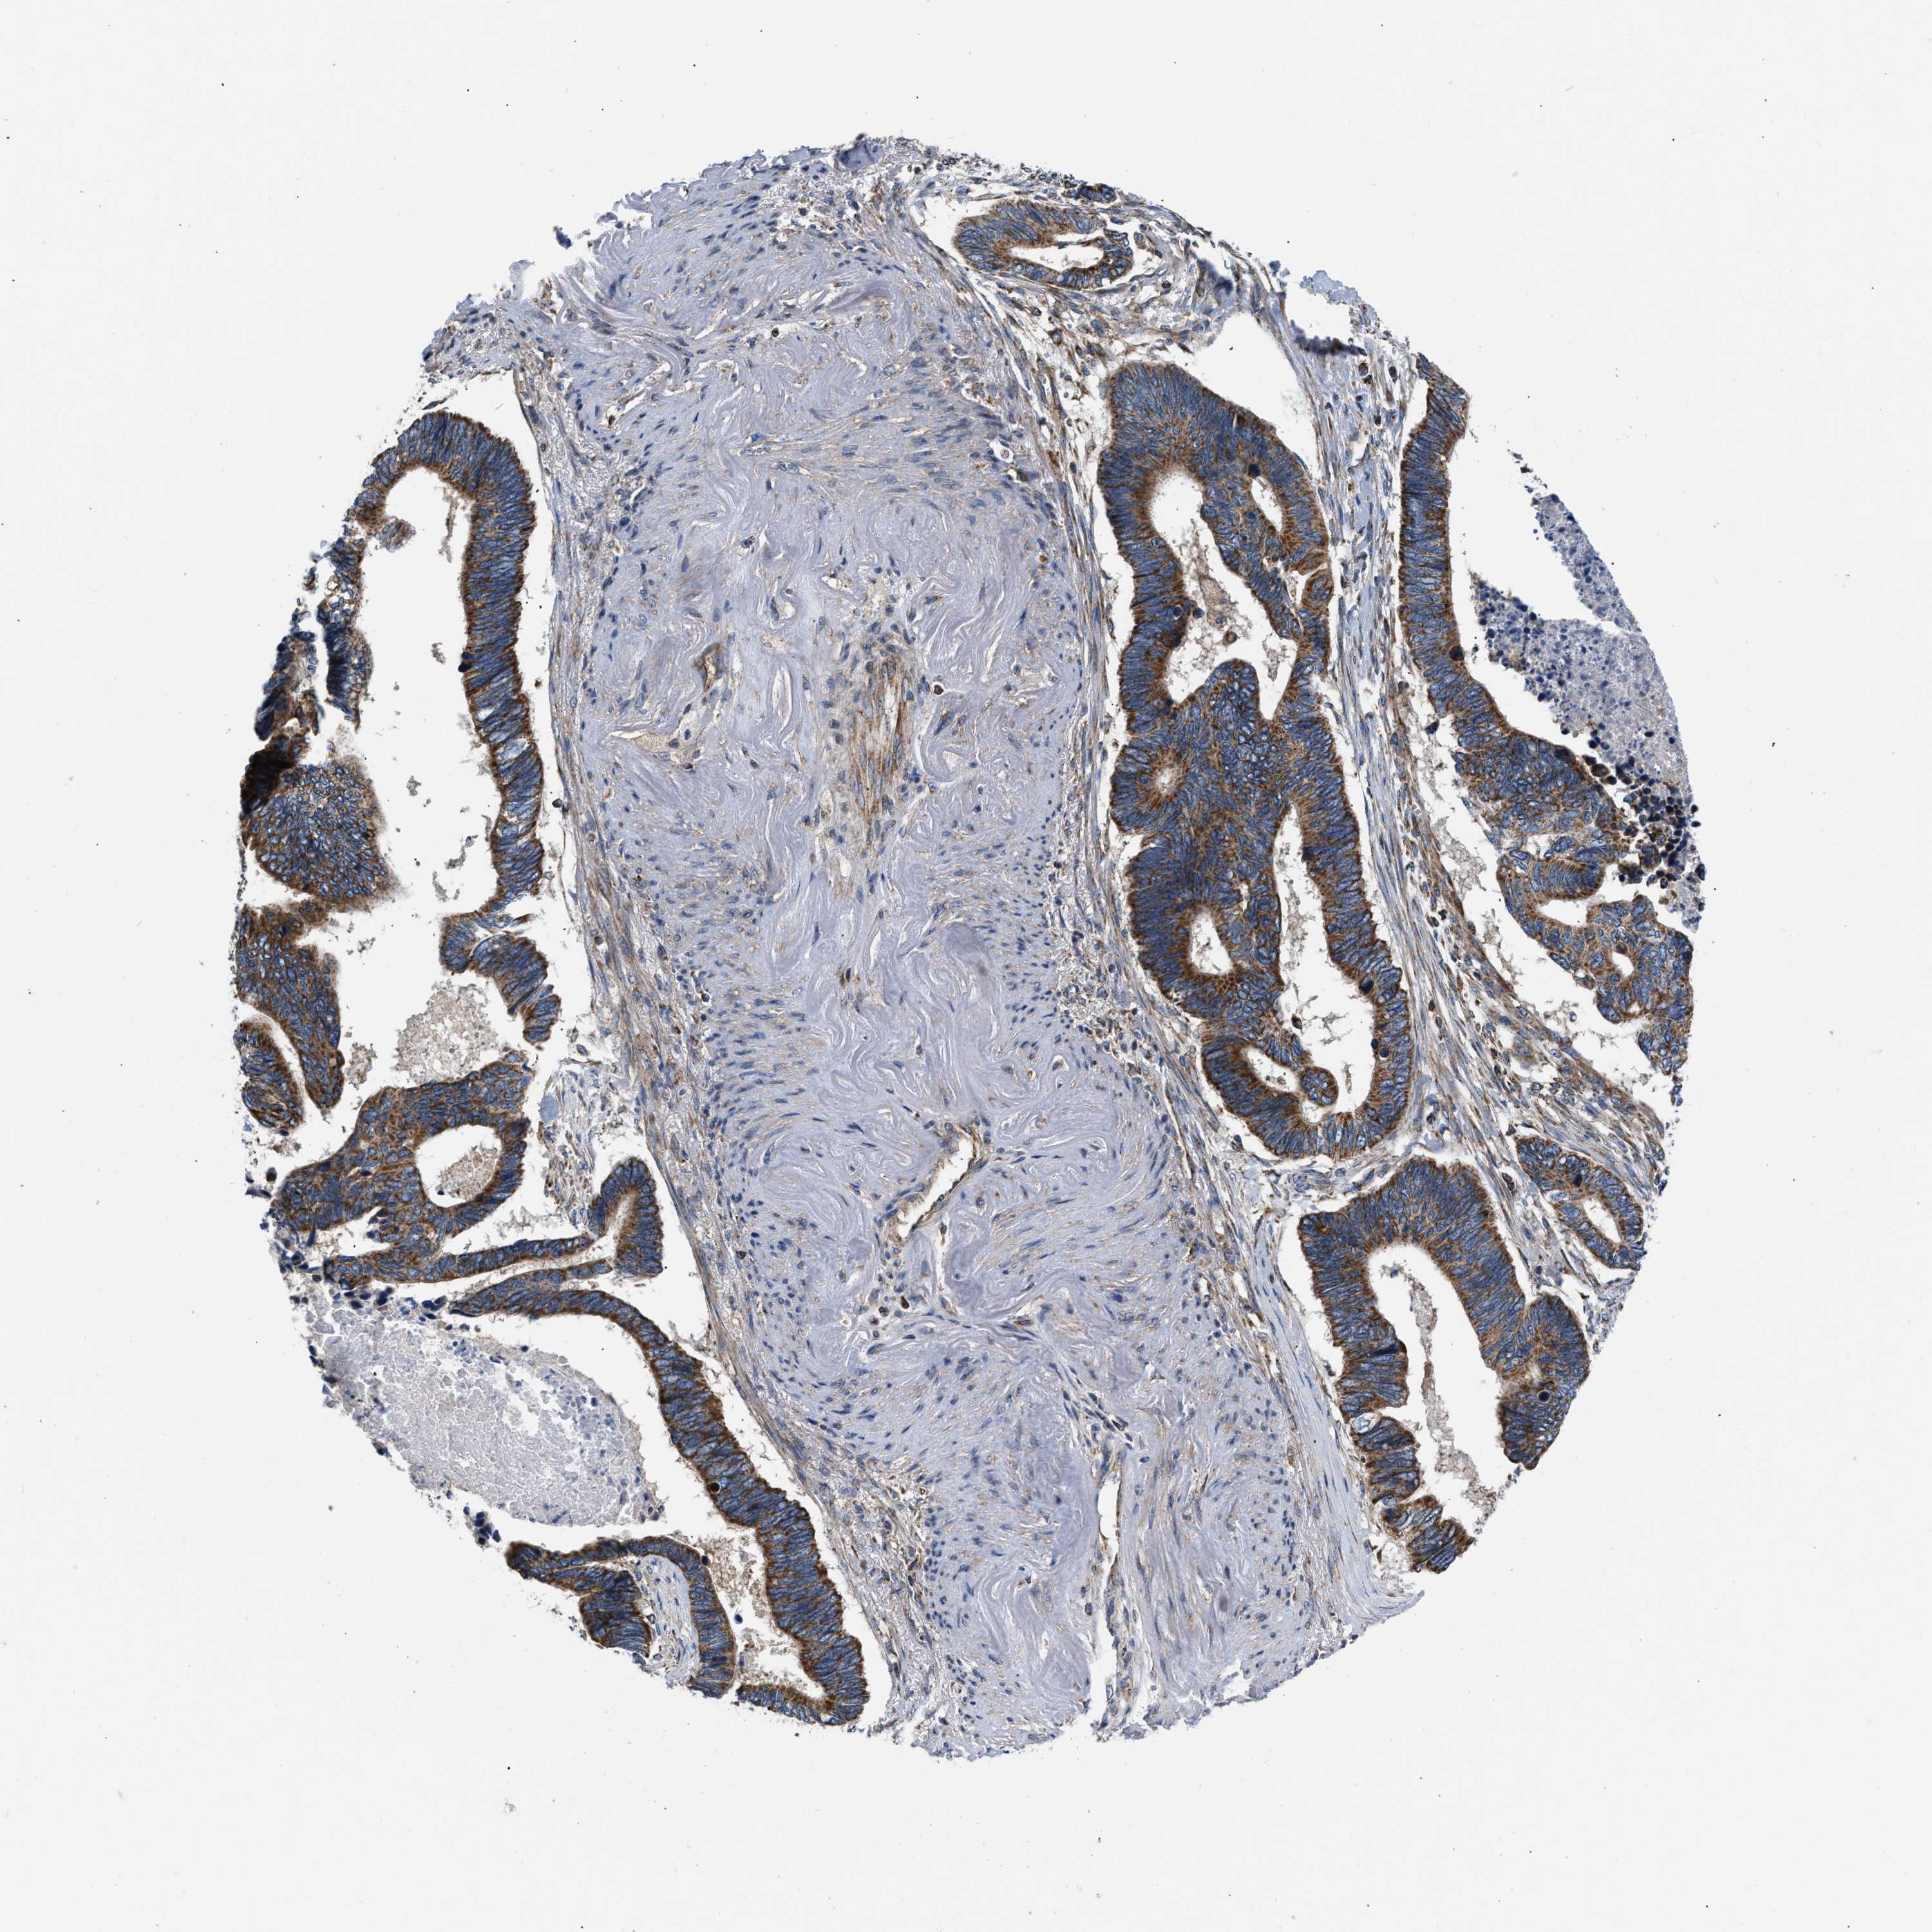

PANCREATIC CANCER - Protein expressioni

A mouse-over function shows sample information and annotation data. Click on an image to view it in a full screen mode. Samples can be filtered based on level of antibody staining by selecting one or several of the following categories: high, medium, low and not detected. The assay and annotation is described here.

Note that samples used for immunohistochemistry by the Human Protein Atlas do not correspond to samples in the TCGA dataset.

Antibody stainingi

Antibody staining in the annotated cell types in the current human tissue is reported as not detected, low, medium, or high, based on conventional immunohistochemistry profiling in selected tissues. This score is based on the combination of the staining intensity and fraction of stained cells.

Each image is clickable and will lead to virtual microscopy that enables deeper exploration of all samples and also displays staining intensity scores, fraction scores and subcellular localization as well as patient and tissue information for each sample.

Antibody HPA003279

Antibody HPA003360

Antibody CAB019303

Staining

High

Medium

Low

Not detected

Intensity

Strong

Moderate

Weak

Negative

Quantity

>75%

75%-25%

<25%

None

Location

Nuclear

Cytoplasmic/membranous

Cytoplasmic/membranous,nuclear

Adenocarcinoma, NOS

Adenocarcinoma, metastatic, NOS